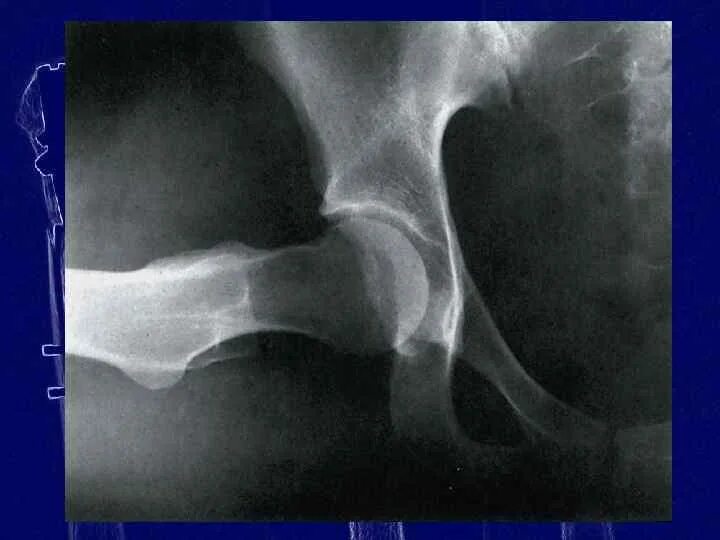

Рентген тазобедренный в двух проекциях